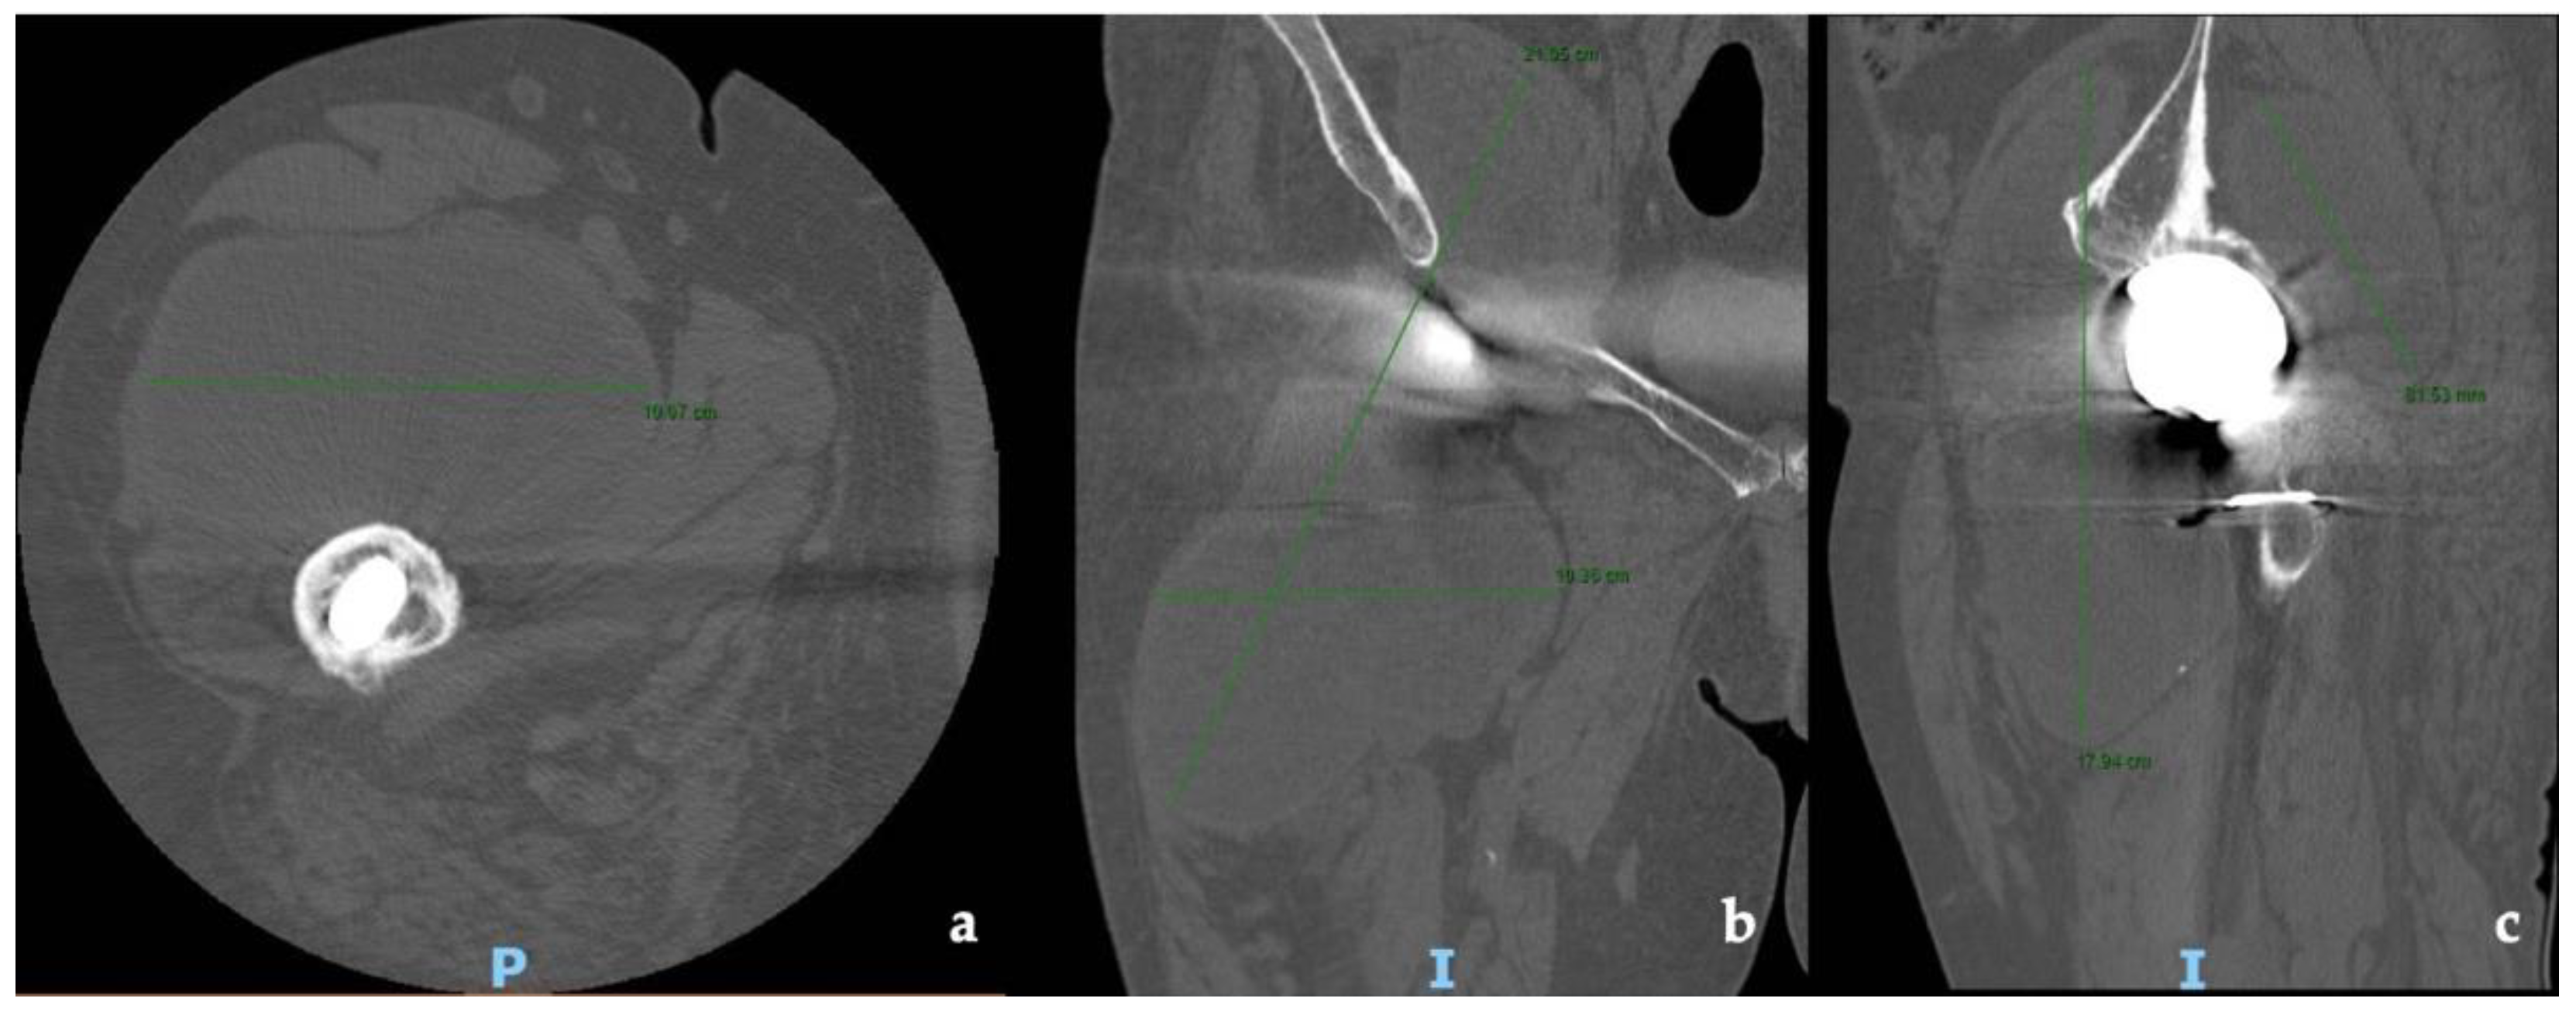

2. Case Report